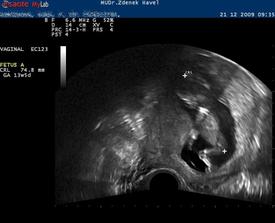

Takže první potrat byl 19.3. 2009, ve 12tt. Srdíčko bylo od 6tt a vše vypadalo krásně a bezproblémově. S doktorem jsme si pár dní před ultrazvukem říkali, že ted už budou končit nevolnosti a už bude jen dobře... no nebylo..zamlklý potrat.

Druhej potrat byl v 10tt. Ten byl spontální. tam to až takové překvapení nebylo, od začátku bylo něco špatně, plod se nevyvýjel a na srdíčko jsme čekali marně.

Třetí portat...zamlklé těhotenství v 20tt. Bylo to to nejhorší co jsem do té doby zažila. Náš chlapeček, byl ještě pár dní předem v pořádku, cítila jsem ho kopat, v 18tt těhotenství viděla mrskat se na ultrazvuku..Triply vyšly taky dobře. Když mi, ale doktor v tom dvacátém řekl, že se nehýbe, tvrdila jsem mu, že jen spí. Nemohla jsem tomu uvěřit, když všechno do té doby bylo dobré a malý tak pěkně prospíval. Nikdy nezapomenu na poslední pohled na ultrazvuk, jak si tam tak leží, s ručičkou před obličejíčkem..... a nikdy nezapomenu na to hnusné datum 8.2., kdy jsem se to dozvěděla a 10.2. 2010, kdy jsem malýho v Trutnovské porodnici porodila.